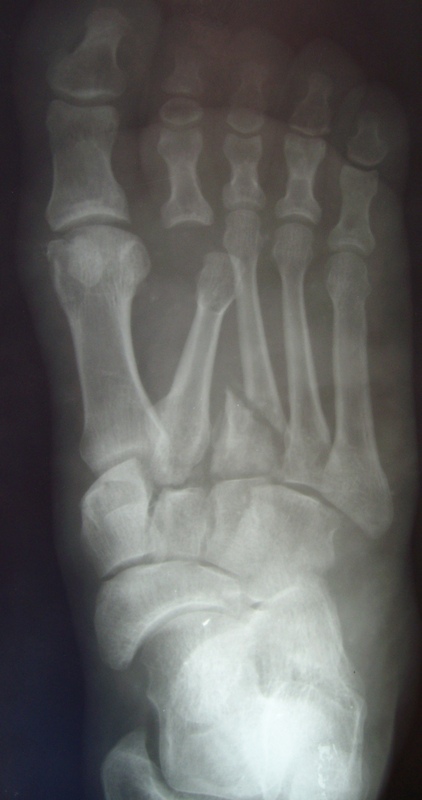

Больной с деформацией стопыБольной К., 36 лет.Травма в 2006 г.-падение с высоты.

Лечился по поводу перелома D- 12 позвонка с нижним парапарезом и оскольчатых переломов плюсневых костей левой стопы. Производился остеосинтез переломов плюсневых костей левой стопы спицами.В 2007 году произведена стабилизирующая операция на позвоночнике с ламинэктомией и фиксацией металлоконструкцией и операция артродез левого голеностопного, подтаранного, таранно-ладьевидного, межклиновидных суставов с фиксацией винтами. В 2008 г. часть винтов удалена. Больной отмечает появление парестезий и движений в пальцах обеих стоп в этом году ( ежедневно пользуется миостимулятором Аб Троник).В настоящее время жалобы на деформацию и нестабильность в левой стопе, боль в области голеностопного сустава, в области пятки (проекция винта).

При осмотре имеется плоско-вальгусная деформация левой стопы, болезненность в пяточной области в проекции винта, тугоподвижность в области шопарова сустава. На тыльной поверхности рубцы. План лечений: удаление винта с подошвенной области, корригирующий реартродез в щопаровом суставе. Как удалить остатки винта? Возможно, понадобится реартродез голеностопного или подтаранного сустава.

The patient, 36 years.

Trauma in 2006 г.-falling from height. It was treated in occasion of fractur D-12 vertebra with bottom paraparesis and splintered fractures of metatarsal of left foot. The osteosynthesis of metatarsal bones was made by wires.

In 2007 stabilizing operation on a backbone with laminectomy and arthrodesis of ankle,subtalar, talo-navicular, intecuneiform joints with fixing by screws . In 2008 the part of screws is removed. The patient marks{celebrates} occurrence movements in fingers of both stop in this year.

Now patient complains to deformation and instability in left stop, a pain in the area of ankle joint and in the field of a heel (a projection of the screw).

At survey there is valgus and planus a deformation of left foot, morbidity in calcaneal area in a projection of the screw,the motion in the midfoot. There is the hems on a back surface of foot.